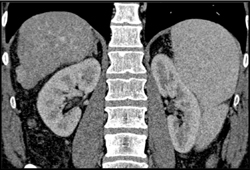

Diagnosis

1cm Hepatocellular Carcinoma (HCC)